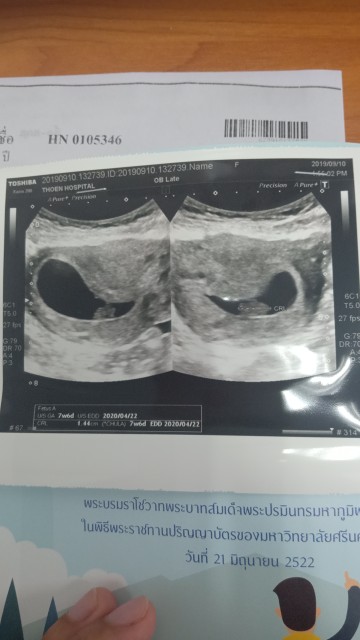

7weekกว่าๆค่ะ

ภาพแรก7week 6day.